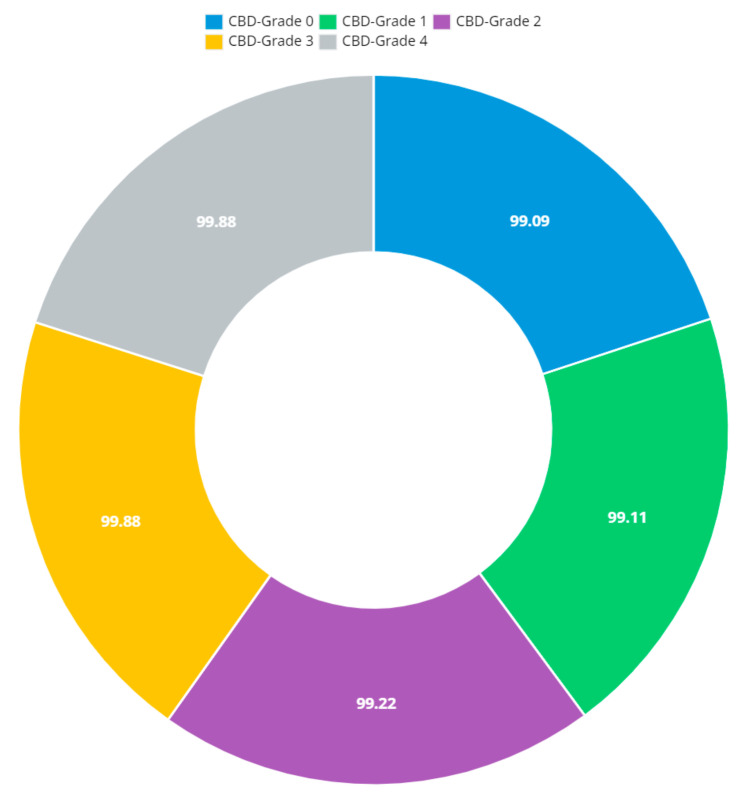

The presented model achieved 99.10% accuracy on the whole test set. The confusion matrix of the presented method is shown in Figure 8, and its performance is compared in detail to that of current methods in Table 5. In Figure 8, we examine the training and learning procedure as a whole to assess the planned activity’s success. Table 6 demonstrates the highest accuracy rate for classifying CBD grades zero–three–four knee joints. The knee joints with a CBD grade of one or two are the toughest to categorize. As can be seen in Figure 8, there is only a marginal amount of room for error when classifying knee joints as CBD Grades zero, three, or four. Knee joints that are classified as CBD Grades one or two have a small number of marginal misclassifications. In several circumstances, the proposed approach incorrectly estimated CBD Grade two as Grade one and vice versa. Joint space narrowing and bony spur development are significantly different in CBD Grade four knee joints. However, CBD-grade one knee joints show little change in JSN or osteophyte growth compared with the other classes. Types of knee RA and their intensity levels are shown in Figure 5. Table 8 and Figure 9 illustrate the JSN accuracy of the proposed and other state-of-the-art methods comparison.

Table 10: Consensus-based decision grade outcomes.

| Grade-CBD | Classification of Knee RA Associated with Domain Adaptation | |||

|---|---|---|---|---|

| Recall | Accuracy | F1-Score | Precision | |

| CBD-Grade 0 | 99.09 | 99.13 | 99.18 | 98.95 |

| CBD-Grade 1 | 99.11 | 99.16 | 99.25 | 98.98 |

| CBD-Grade 2 | 99.22 | 99.39 | 99.34 | 99.21 |

| CBD-Grade 3 | 99.88 | 99.59 | 99.51 | 99.41 |

| CBD-Grade 4 | 99.88 | 99.62 | 99.57 | 99.44 |

Figure 12 shows that the presented system outperformed other methods in terms of sensitivity (Se), specificity (Sp), precision (Pr), accuracy (Acc), and dice score (Ds), demonstrating deep learning’s capability. Figure 13 depicts the CBD grade outcome doughnut chart. In this research, the presented model increased overall ROI detection accuracy by up to 0.5 percent and improved classification accuracy by up to 1.18 percent. The proposed model is more dependable as a result of the detailed knee JSN characteristics. The improvement was satisfactory, and we agree with the observation that the AP view has a significant portion of the information necessary to assess the severity of knee RA with the CBD grading system. The CBD score is often examined using the AP view alone. Table 6 presents a comparison of the output of the proposed methodology with that of other methods that are currently in use. R K Ahalya et al. (2022) obtained Se of 0.9491, Sp of 0.9408 Pr of 0.9213, Acc of 0.9551 and Ds 0.8991; Uma Ramasamy et al. (2022) achieved Se of 0.8891, Sp of 0.8982, Pr of 0.8844, Acc of 0.9012, and Ds of 0.8923; Shawli Bardhan et al. (2021) obtained Se of 0.9785, Sp of 0.9561, Pr of 0.9713, Acc of 0.9864, and Ds of 0.9231; Rabbia Mahum et al. (2021) achieved Se 0.9815, Sp of 0.9789, Pr of 0.9896, Acc of 0.9714, and Ds of 0.9795; Kristine et al. (2022) obtained Se of 0.9012, Sp of 0.9101, Pr of 0.8915, Acc of 0.9211, and Ds of 0.9117; Shawli Bardhan et al. (2020) achieved Se of 0.8889, Sp of 0.8541, Pr of 0.8114, Acc of 0.8671, and Ds of 0.8781; and Sujeet More et al. (2022) obtained Se of 0.9622, Sp of 0.9771, Pr of 0.9831, Acc of 0.9685, and Ds of 0.9121. Our active deep CNN model acquired a knee joint identification accuracy of 98.97% and a knee RA severity classification accuracy of 99.10% using the presented methodology. This model also gives superior performance to handmade features. The active deep CNN model that we have presented and the pre-trained domain adaptation models that are employed in our system produce improved prediction accuracy outcomes for the five classes of knee RA that were experimentally determined.